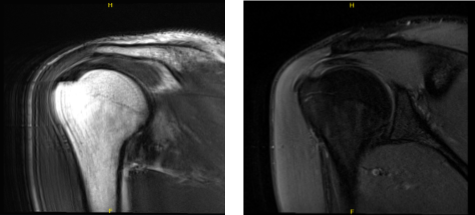

MRI were reviewed and discussed; Acromioclavicular Joint: The undersurface of the acromion is curved. There is mild acromioclavicular joint arthrosis. Rotator Cuff: There is a partial-thickness tearing the superior subscapularis tendon. There is tendinosis in the supraspinatus tendon.

The infraspinatus, and teres minor tendons are intact. There is no disproportionate muscle atrophy. The rotator interval is normal. Biceps And Labrum: The long head of the biceps’ tendon is intact and maintained in the bicipital groove. The labrum and biceps labral anchor are intact. Glenohumeral Joint:

There is a physiologic amount of fluid within the joint. The articular cartilage is maintained. Bones: There is no acute fracture or osteonecrosis. There is no suspicious bone marrow edema. Bursae: There is no significant subacromial-subdeltoid bursitis.

Miscellaneous: The deltoid muscle is maintained. There is no significant axillary lymphadenopathy. The subcutaneous tissues are within normal limits. Which means the shoulder’s MRI showed that there is a rotator cuff tear along with acromial spur and AC arthritis of the right shoulder.

MRI Right shoulder non-contrast